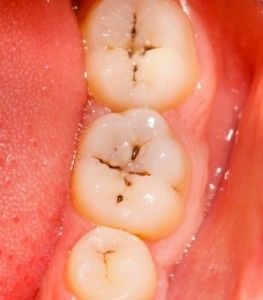

One of the most overlooked areas in a dental practice today is the Caries Risk Assessment. (CAMBRA) It happens a lot that offices do not have a protocol in place to assess and prevent caries. CAMBRA is not new. The California Dental Journal produced two journals dedicated to this topic in October and November 2007 and again in October 2011.

- Caries risk assessment provides information pertaining to three specific overarching domains: white spot lesions, decalcification enamel. defects or other obvious decay in the child.